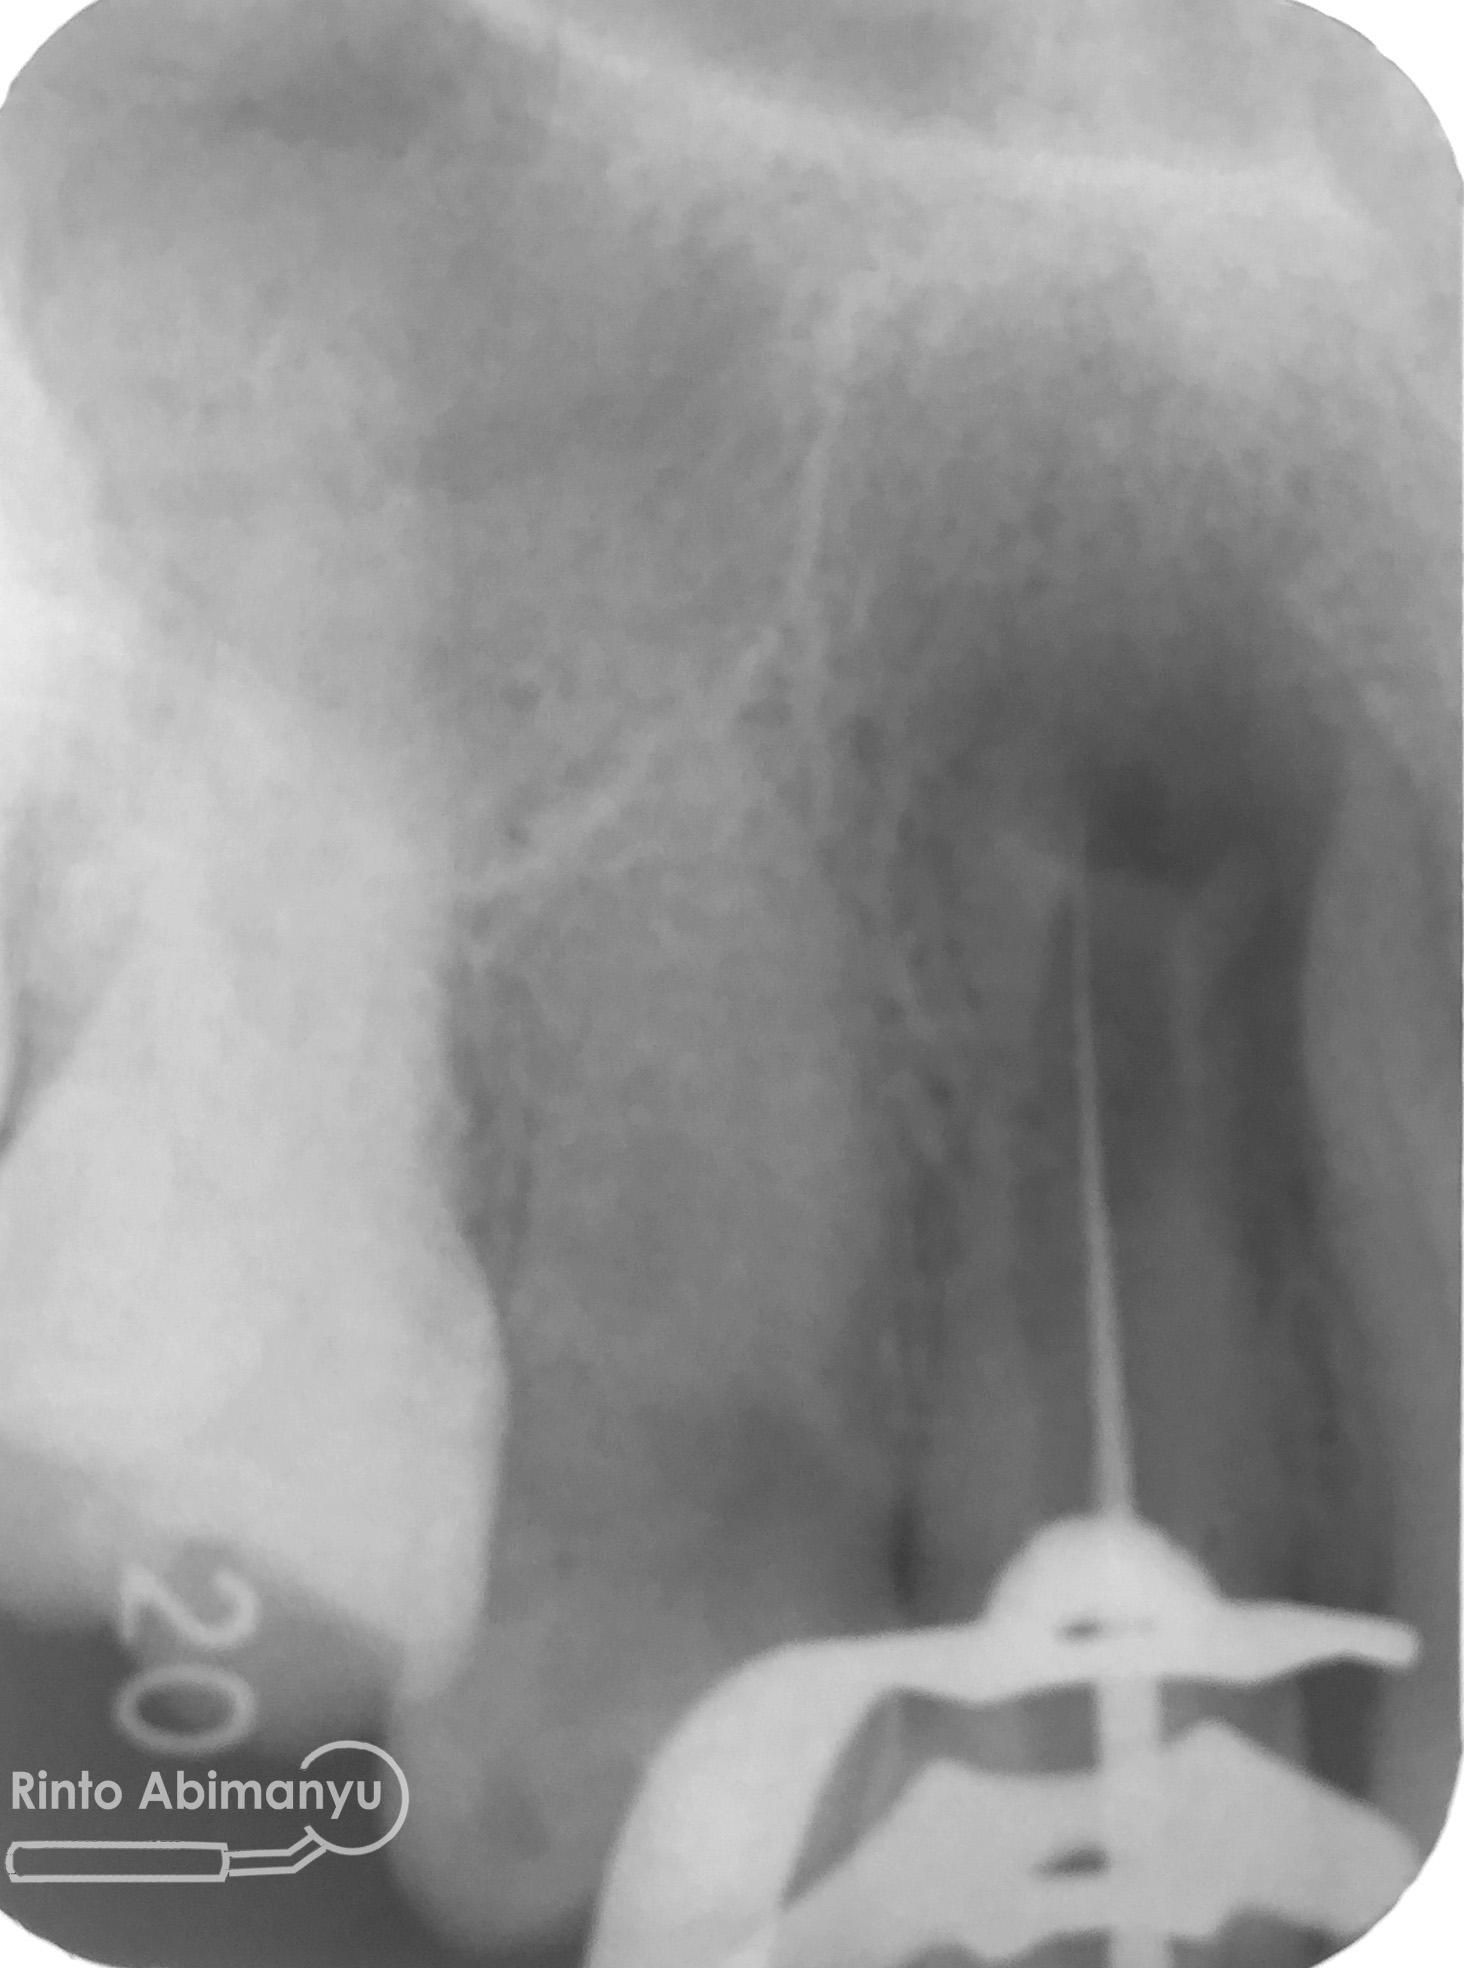

Setelah melihat hasil ronsen trial guttap maka pengisian siap dilakukan… Untuk pengisian saluran akar saya memakai tehnik warm vertival condensation memakai alat Element Obturation Unit (SybronEndo) dan siler AH plus (Dentsply)…

Setalah pengisian usahakan kamar pulpa dibersihkan dari sisa2 siler dan kotoran2 agar bahan adhesive yang kita pakai untuk restorasi dapat melekat maksimal.. Untuk basis saya menggunakan X-tra Base (Voco) kemudian diatasnya memakai komposit Z 350 XT (3M)…

Setelah itu dilakukan pengambilan ronsen kembali…

Alhamdulillah perawatan ini tidak ada kendala dan bisa diselesaikan dalam satu kali kunjungan langsung dua gigi… Ronsen sangat penting dalam prosedur perawatan saluran akar, jadi pesan saya adalah “No Xray, No Endo” 🙂